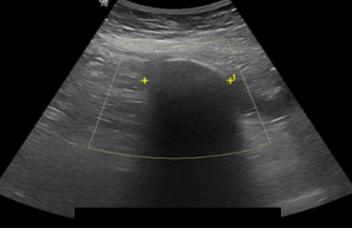

Laboratory tests showed electrolyte imbalance in 14 patients (87.5%) and liver function tests abnormalities in five patients (31.2%). A correct preoperative diagnosis of GI was reached in 13 patients (81.2%); the remaining was diagnosed during surgery. The classical image signs of GI were visualized in 7 patients (43.7%) on plain abdominal radiograph (Figure 1), in six patients (37.5%) on ultrasound (Figure 2) (Figure 3), and in 13 patients (81.2%) on CT (Figure 4) (Figures 5a & b).

Figure 2 Abdominal ultrasound shows a hyperechoic oval-shaped image of 3.6 cm with acoustic shadow suggestive of a gallstone located in the right lower quadrant of the abdomen.

Figure 3 Abdominal ultrasound reveals an endoluminal hyperechoic round-shaped image with acoustic shadow located lateral to mesogastrium.